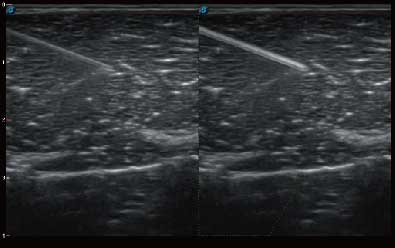

结合DB中国旗舰官方网站超宽频带探头技术优势,能够更好地获得高分辨力与高穿透力的平衡,保证图像质量,为临床诊断保驾护航。

微米成像技术提升了对组织斑点噪声信号的抑制能力,并进一步强化边界信息,从而获得清晰图像。